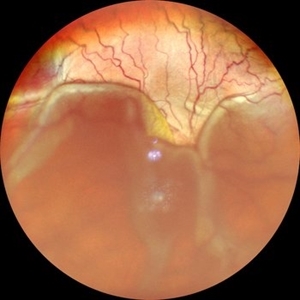

RHEGMATOGENOUS RETINAL DETACHMENT

WIDE-FIELD COLOUR FUNDUS PHOTOGRAPH OF AN 8 YEAR OLD MALE CHILD WITH RHEGMATOGENOUS RETINAL DETACHMENT

Photographer: Dr. Akansha Sharma-Retina Foundation, Ahmedabad

Condition/keywords: Retinal Detachment, rhegmatogenous retinal detachment